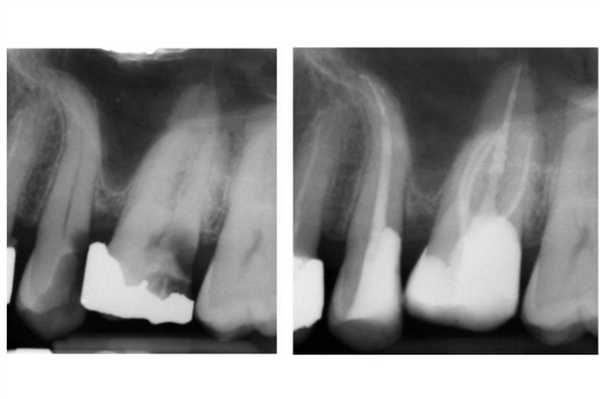

Фото 1. Повторное эндодонтическое лечение и фиксация E.max накладки на зуб LR6 a) Рентгенограмма до ревизии канала. b) Повторное лечение корневого канала и формирование композитной культи. Пациент был направлен к своему лечащему стоматологу для выполнения реставрации с перекрытием бугров. с) Препарирование под накладку; дистальный край сформирован на композитной основе. d) Изоляция коффердама перед фиксацией. e) Изолирование соседних зубов при помощи тефлоновой ленты. f) Фиксация накладки на композитный цемент. g) Очистка излишков цемента. h) Вид после фиксации.

DME менее важен при использовании традиционных цементов (цинк-фосфатных или СИЦ) для фиксации непрямых реставраций. Данные материалы мене чувствительные к промахам изоляции, а их излишки могут быть удалены после полной полимеризации. Однако в подобных случаях достаточно сложно получить качественный оттиск (фото 2).

Фото 2. Лечение корневых каналов и формирование композитной культи на зубе LL6. Пациент был направлен к лечащему врачу для изготовления накладки с перекрытием бугров. Золотая накладка была зацементирована на Fuji Plus. Дистальный край находился под десной, а край накладки был сформирован на композитной реставрации (DME). Граница препарирования на всех поверхностях находилась в границах тканей зуба, кроме дистальной поверхности. Рентгенограмма, полученная через год, демонстрирует признаки заживления периапикального поражения.